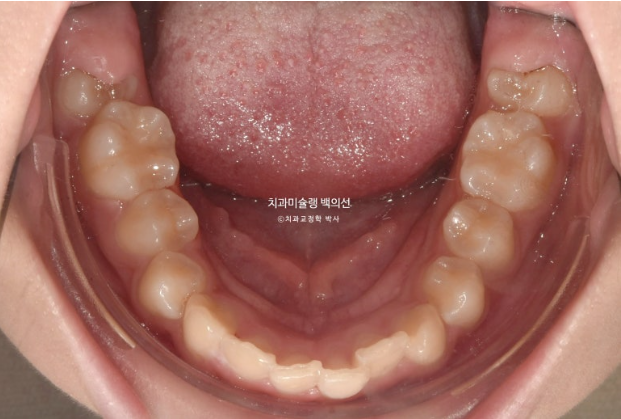

24년 10월부터 25년 4월까지 6개월간 18개 장치를 더 낀 후 치료를 마무리 했습니다.

25.04

중심선은 정확하게 맞으며 과개교합이 잘 해소되었습니다.

어금니 교합은 물샐틈 없는 1급입니다.